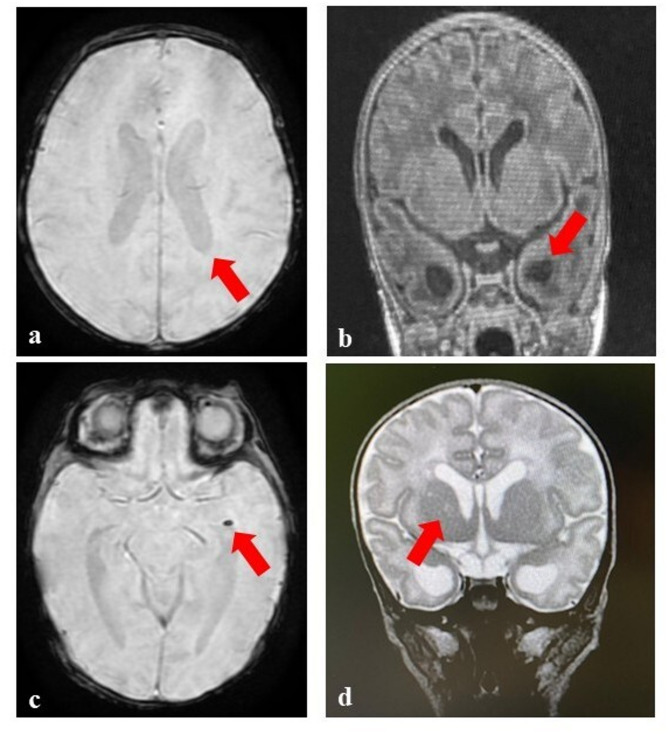

Case presentation: We report on a male term newborn showing in the first days of life hyperexcitability, tremors and increased muscular tone, in addition to thrombocytopenia, initially related to an early-onset sepsis. Obstetric history revealed that the mother underwent steroid treatment during the whole first trimester of pregnancy. She had positive CMV IgG and negative CMV IgM antibodies throughout gestation. At 15 days of age, due to the persistence of neurological and hematological signs and abnormalities found on brain ultrasound (bilateral ventriculomegaly, and an anechoic lesion within the right caudothalamic grove at first related with grade I intraventricular hemorrhage) a brain magnetic resonance imaging (MRI) was performed, showing significant lesions highly suggestive of cCMV. Although such diagnostic hypothesis was unsuspected (in light of the association of clinical manifestations with perinatal sepsis and the misleading maternal serology), however CMV DNA detection on blood and urine was carried out, giving positive results in both samples for connatal infection diagnosis. Newborn CMV IgG and IgM antibodies resulted positive, while the IgG avidity test showed high values according to a likely early intrauterine infection. The antiviral therapy was therefore begun and continued for 6 months. He currently is 6 months old and included in a multidisciplinary follow-up. His growth is within the normal limits, but a neuromotor delay is present. Audiological and ophthalmological evaluations, laboratory as well as multiorgan ultrasound (US) examinations have not revealed further anomalies to date.

Conclusions: Our case underlines that CMV reactivations or reinfections may be responsible, as well as PI, for significant and harmful effects on the fetus and newborn. It also shows the limited diagnostic and preventive/therapeutical weapons available against NPI during gestation. The present experience confirmed, indeed, the literature regarding the absence of valid laboratory test to identify women with preexisting immunity at risk of giving birth to an infected neonate. Women with previous immunity should be treated with precautionary protocols, including US monitoring and fetal MRI aimed at detecting cCMV. Brain MRI findings may be a pre-warning for newborns of mothers with previous immunity showing neurological symptoms and ultrasound abnormalities. In these cases, its execution may allow the identification of pathognomonic lesions.